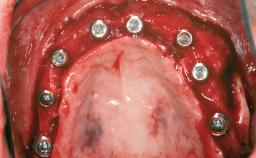

Iliac and Calvarial Bone Blocks for Onlay Grafting of a Severely Resorbed Edentulous Maxilla

| # of Implants | 8 |

| Type of Implants | Reduced-Diameter|Two-Piece |

| Attachment | Reduced-Diameter|Two-Piece |